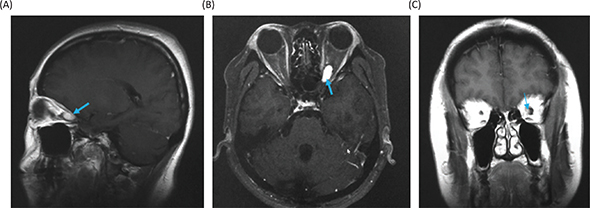

When her father underwent surgical treatment for a cystic cerebellar hemangioblastoma at our hospital (International University of Health and Welfare Atami Hospital), she visited our hospital, at the age of 36, because of recently developed visual disturbance. Her visual acuity decreased gradually and her visual filed became narrow. The visual acuities at the first visit to our hospital were 0.1 on the right side and sensus luminis on the left side. The examination of her left ocular fundus showed a pale papilla (Figure 3).

Fig 3

Figure 3. Optic fundi before radiosurgery. (A) Left healthy side. (B) Right lesion side.